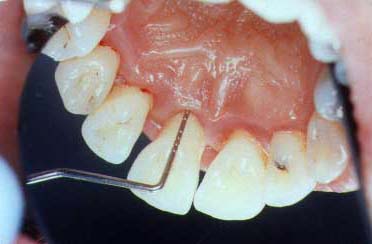

gum disease

A Diseased Area

(All diseased areas don't look the same)

The gum tissue is slightly redder than normal and there are slight changes in the gum tissue form. There is some yellow pus on the gum margin where the periodontal probe will be inserted in the next photo.

periodontal probe in pocket

Probe in the Pocket

This print shows the probe in the pocket to a depth of 8 mm.

periodontal probe outside pocket

Probe Outside of the Pocket

You can see how deep the probe did actually go into this disease pocket. This is approximately 8 millimeters and shows how much gum and bone destruction has occurred